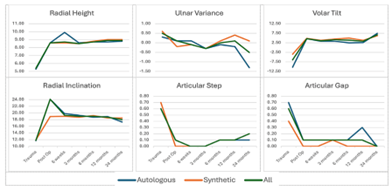

Radiological outcomes

Radiological outcomes, including union, reduction, and graft resorption, were favorable. All fractures achieved union, with an average time to union of two months (range four to 16 weeks). No cases resulted in non-union requiring re-grafting, and radiological parameters were consistently maintained over time (Figure 4).

Figure 4: Series of graphs showing the radiological outcomes (radial height, ulnar variance, volar tilt, radial inclination, articular step, and articular gap) obtained over time.

Intra-articular fractures did not exhibit loss of articular reduction, leading to significant intra-articular step and gap. There were no notable differences in time to union or maintenance of fracture reduction when comparing outcomes of autologous and synthetic bone grafts. Radiological arthritis was detected in nine out of the 59 patients in which we utilized bone grafts. Among these cases, five patients had received autologous bone grafts, while four patients had received synthetic bone grafts.